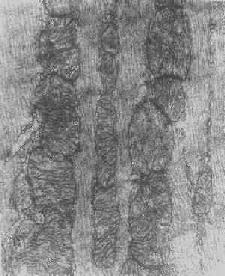

线粒体肿胀(基质型)空泡变(心肌缺氧)

图1-11 线粒体肿胀(基质型)空泡变(心肌缺氧)

根据细胞损伤的种类和性质,可在线粒体基质或嵴内形成病理性包含物。这些包含物有的呈晶形或副晶形(可能由蛋白构成),如在线粒体性肌病或进行性肌营养不良时所见(图1-12);有的呈无定形的电子致

线粒体内晶形包含体(进行性肌营养不良症)

图1-12 线粒体内晶形包含体(进行性肌营养不良症)

密物,常见于细胞趋于坏死时,乃线粒体成分崩解的产物(脂质和蛋白质),被视为线粒体不可复性损伤的表现。线粒体损伤的另一种常见改变为髓鞘样层状结构的形成,这是线粒体膜损伤的结果。